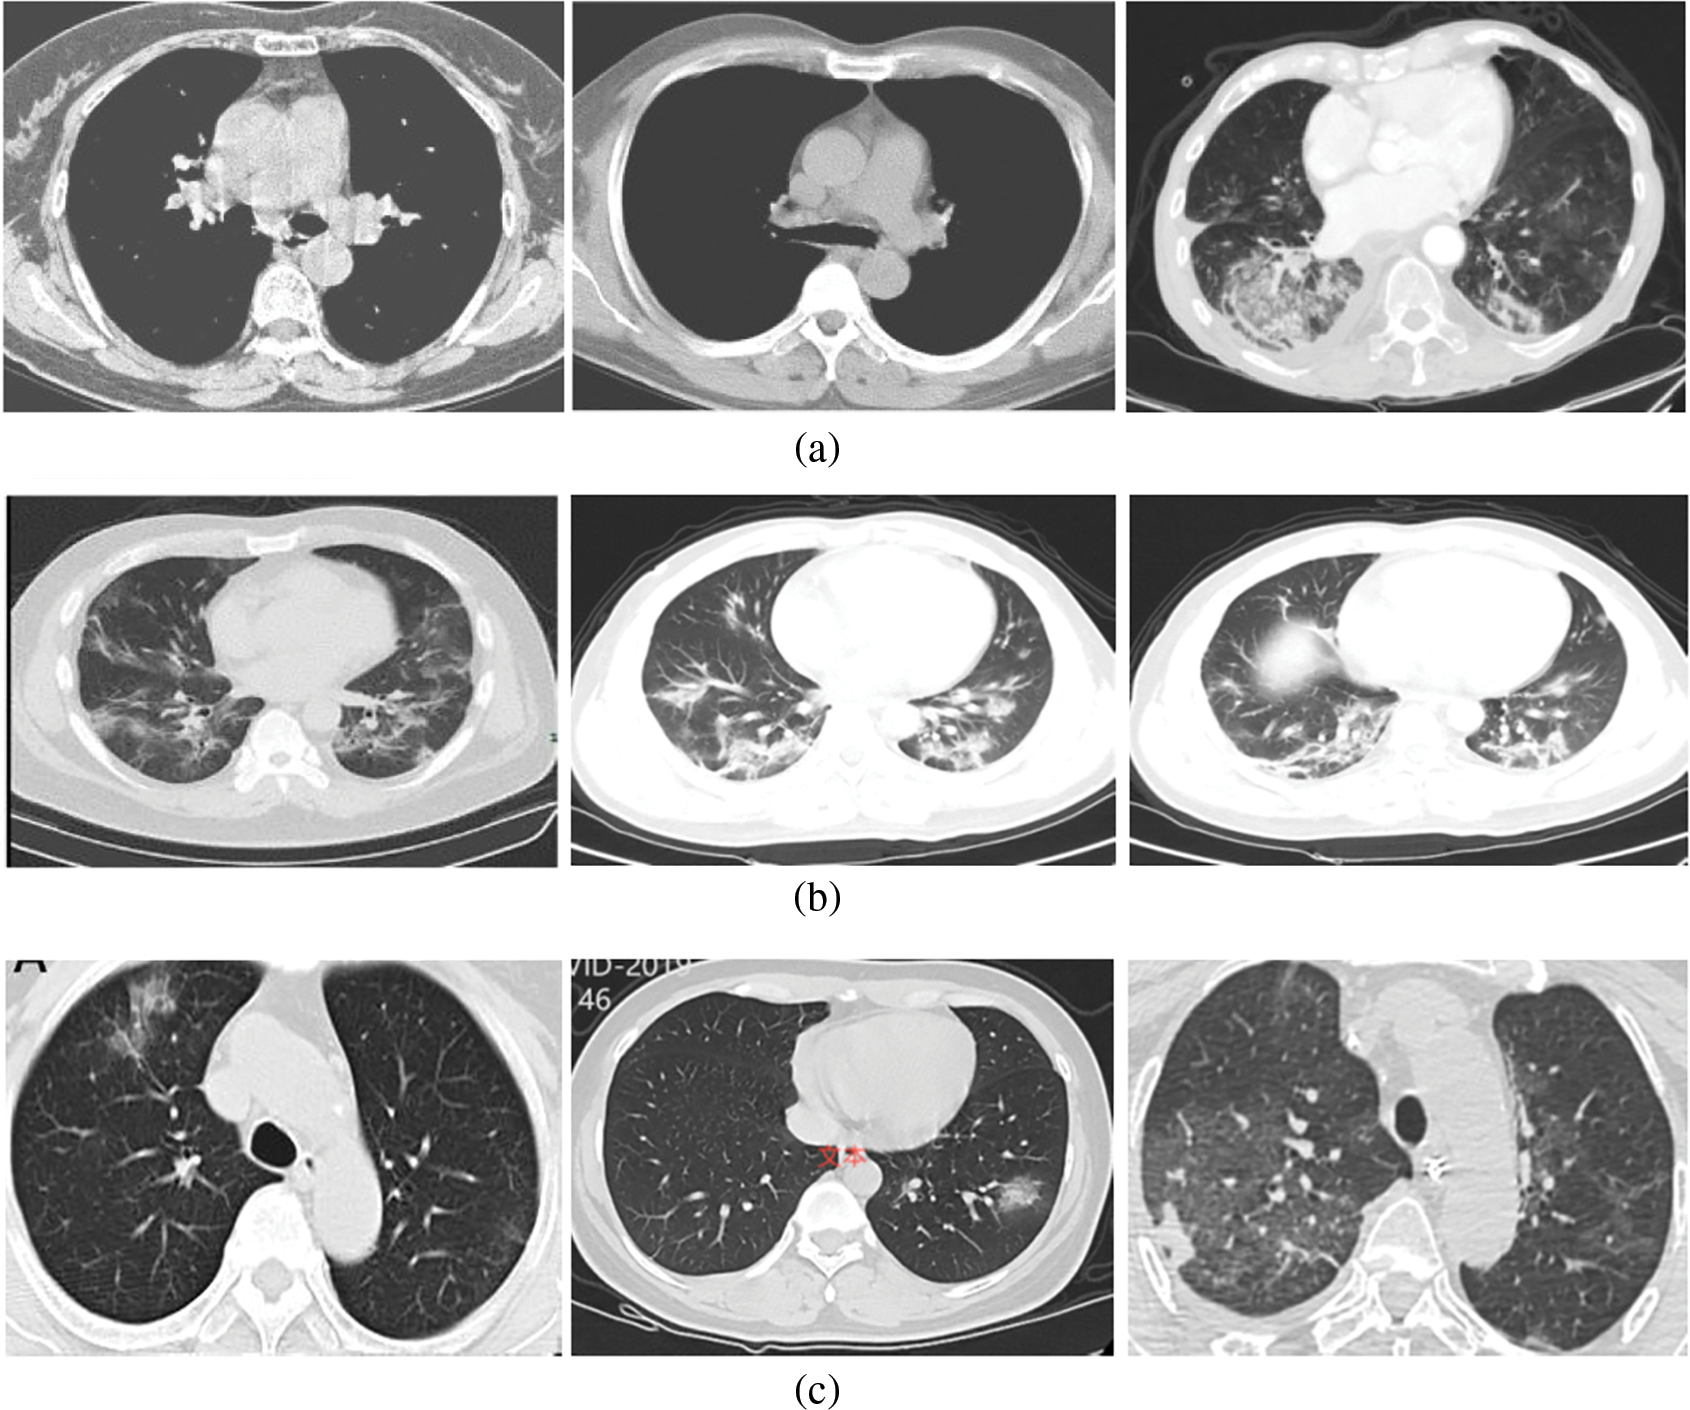

In the CT scan images, 213 severe cases, 236 moderate cases, and 167 normal cases are taken for input. Fig. 3 shows some of the input images from normal, moderate, and severe categories.

Figure 3: (a) Normal (No-COVID) cases (b) Moderate cases (c) Severe cases